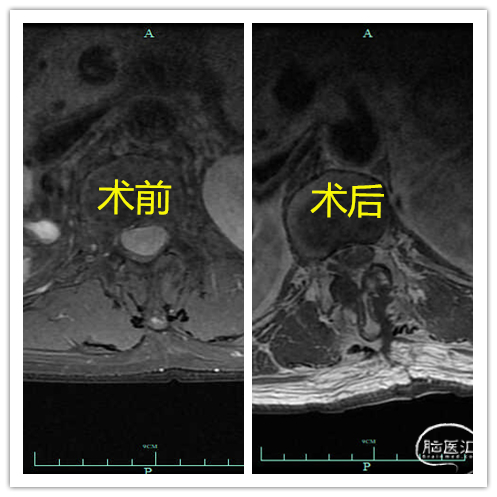

术后复查

图4. 术前后MR矢状位对比